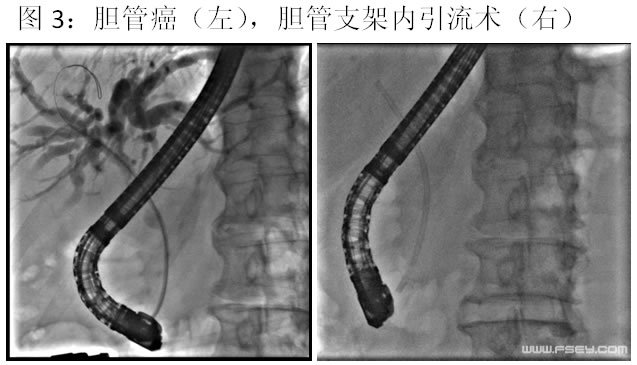

目前我院消化内科已全面开展ERCP诊疗操作,可进行胆管结石、胆管癌等各类胆道疾病的微创诊治,例如内镜下乳头括约肌切开术、内镜下胆管扩张术、内镜下胆管结石取石术、内镜下鼻胆管引流术等,创伤小,恢复快,尤其适合不能耐受或不愿行手术治疗的患者,均取得了较好的疗效。而对于胆管或胰腺肿瘤导致梗阻性黄疸而又失去手术机会或不能耐受手术治疗的患者,可行内镜下胆管支架内引流术,能有效提高生活质量。